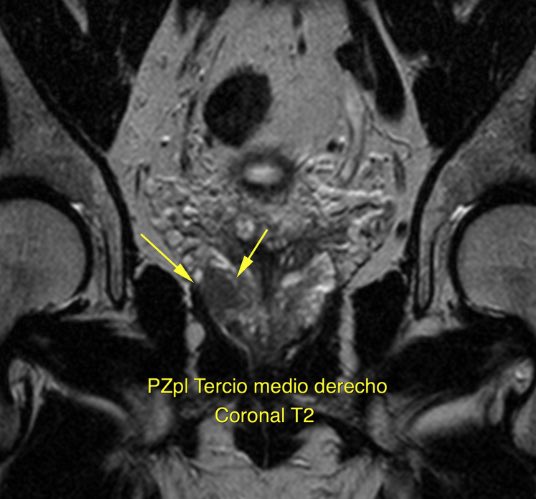

First ThuFLEP procedure successfully performed in Chile with Urolase+ Premium We are proud to share that the first #ThuFLEP procedure in Chile using the Urolase+Premium laser system has been successfully completed at @FelixHfb , with the strong support of our trusted partner IMV MED CHILE. The surgery was performed by Dr. @JIgnacioAcuna and involved a prostate of 50 cc with a non-simple anatomical configuration, further complicated by cystolithiasis with a 17 mm bladder stone. Despite these factors, the entire operation was completed in just 45 minutes. The patient was discharged within 24 hours, underscoring the efficiency and favorable recovery profile of the procedure. @JIgnacioAcuna highlighted the performance of the #DissectPulse mode, noting its precision in anatomical dissection, controlled tissue interaction, and effective hemostasis. According to his feedback, the laser performed excellently and efficiently throughout the case. We sincerely thank IMV MED CHILE for their professional support and collaboration in bringing advanced Thulium Fiber Laser (TFL) technology to Chile. Congratulations to @JIgnacioAcuna and the entire team at @FelixHfb on this achievement. #UrolasePremium #ThuliumFiberLaser #LaserUrology #Endourology #ChileHealthcare #VPGLaserOne